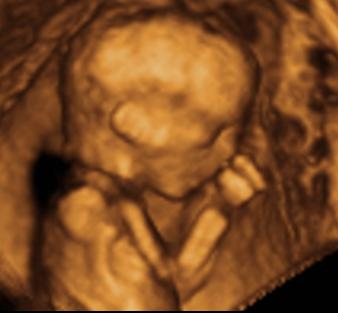

Ind, gyönyörű babád van

– köszi a képeket

Azt még megkérdezem, hogy ti most tulajdonképpen mennyi idősök vagytok? – a kép szerint 27hét+3nap, a vonalzód szerint pedig 26 hét.... – nagyobb a babád, mint kellene?